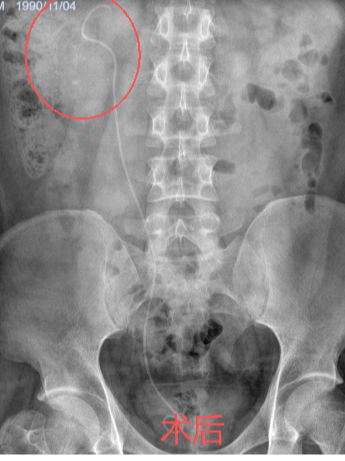

“医生,您帮我看看,我这样的情况能不能不在肾上‘打孔’?”34岁的姚先生拿着自己的CT报告,一脸焦虑地走进市中医医院泌尿外科。报告显示,他的右肾里藏着一颗铸型结石,形状不规则,几乎填满了肾脏空间。外院医生曾建议他做“经皮肾镜碎石取石术”——一种需要在腰部穿刺造瘘的微创手术。一想到术后身上要带着一根肾造瘘管好几天,姚先生犹豫了。泌尿外科副主任杨泽敏仔细阅片后,提出了一个更让他安心的方案——利用先进的高清软镜系统进行“无创清石”,从自然通道进入,碎石的同时直接吸出,体表不会留任何伤口。

效果展示

手术非常顺利,姚先生体内的结石被彻底清除。术后,科室还为他安排了结石成分分析,并开具了个体化的中药汤剂,旨在调理体质,预防复发。从“瞬间清石”到“长期防石”,实现了对泌尿系结石的全程化管理。